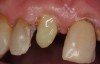

A Class IN maxillary bicuspid was previously restored with a fiber post and an all-porcelain crown (Figure 1). The forces of the oral environment resulted in fracture of the fiber post and crown failure. The remaining fiber post in the root was removed, and anti-rotational areas were prepared for a cast post (Figure 2). A gold cast post was constructed at a dental laboratory, using an indirect technique (Figure 3). A porcelain-fused-to-metal (PFM) crown was constructed with a bevel finish to provide a ferrule and reduce forces on the post (Figure 4 and Figure 5).

Figure 1  X-ray of an endodontically treated second bicuspid restored with a fiber post, core, and all-porcelain crown.

Figure 1

Figure 2  Same second bicuspid as Figure 1 after removal of the fractured fiber post.

Figure 2